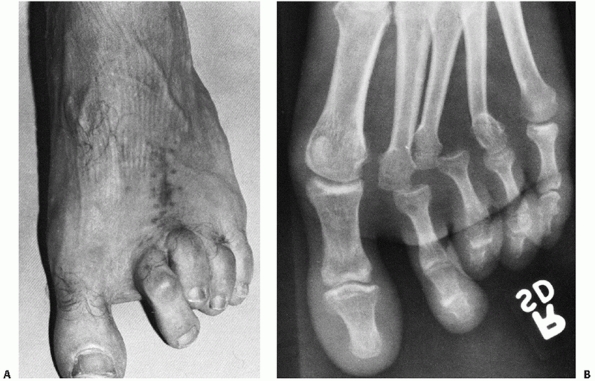

![]() |

FIGURE 60-11 Neuropathic dislocation of the navicular. A. Anteroposterior radiograph with medial deviation of the navicular. B. Lateral radiograph showing plantar migration. C,D. Fixation post reduction for fusion of the naviculocuneiform joints.